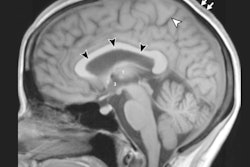

Nine (33%) of the 27 astronauts with more than 30 days of cumulative lifetime exposure to microgravity experienced more cerebral spinal fluid space surrounding their optic nerve, while six astronauts (22%) with more than 30 days in space exhibited flattening of the rear of their eyeball. Four astronauts (15%) in the same group showed bulging of the optic nerve, while three astronauts (11%) displayed changes in the pituitary gland and its connection to the brain.

The same types of abnormalities are seen in cases of intracranial hypertension where no cause can be found for increased pressure around the brain. The pressure causes swelling between the optic nerve and the eyeball and eventually can result in impaired vision.

"Visual acuity degradation in astronauts exposed to microgravity is a newly recognized phenomenon," the authors wrote. "Although the exact mechanism is yet to be fully elucidated, the constellation of MR findings alone suggests that intracranial hypertension is an important component, drawing similarities to [intracranial hypertension] and substantiated by direct [cerebrospinal fluid] pressure measurements in a small subset of astronauts after flight."